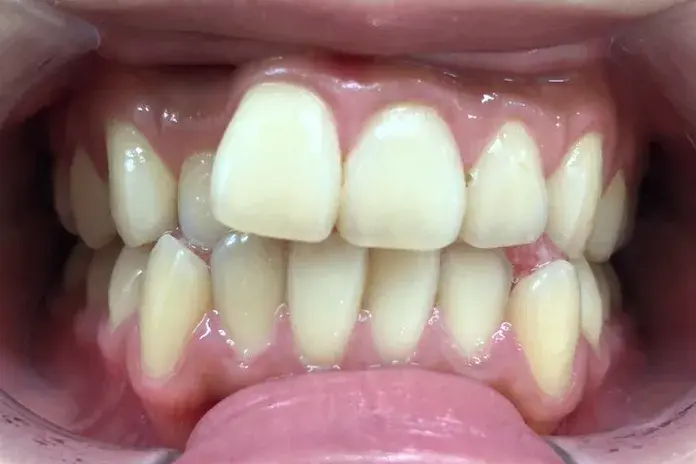

治療期間 4カ月

治療費 23.1万円(月額1,925円~)

※上顎前歯部、下顎前歯部の叢生をマウスピース型矯正装置で改善したケース。矯正治療上のリスクとして、治療中の虫歯、歯根吸収、歯肉炎 ・歯周炎の発生などが考えられる。